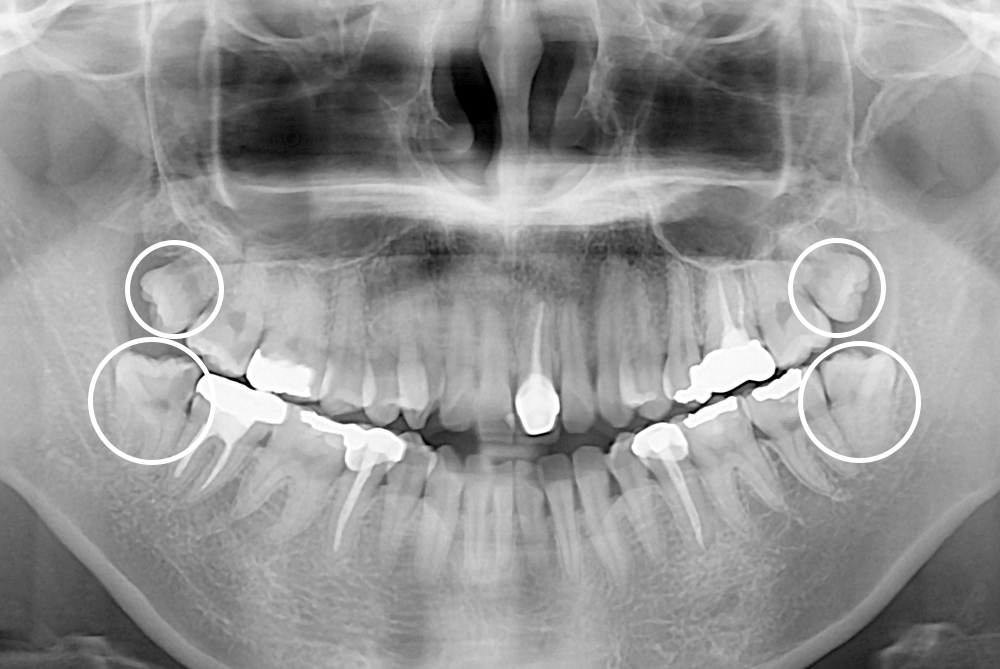

[사랑니] 매복 사랑니 발치

치료전 : 2019-10-16